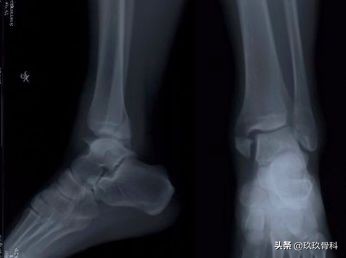

辅助检查

- X线 踝关节正侧位(必要时应加照踝穴位)

应力位片

诊断:体检—疼痛肿胀压痛的部位在踝的前上方;X线—踝内旋20°正位

踝的骨折▲▲▲